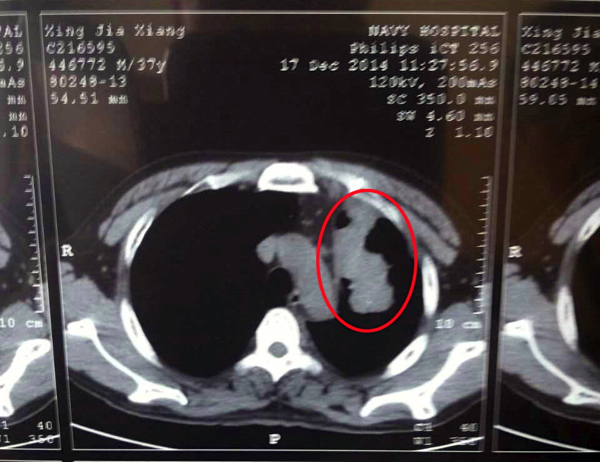

2014年12月17日肿瘤在CT上的显现(被圈部分)

2014年12月17日CT结果是肿瘤大小7.1*3.5cm

2014年12月17日诊断结论:肺腺癌四期(晚期)